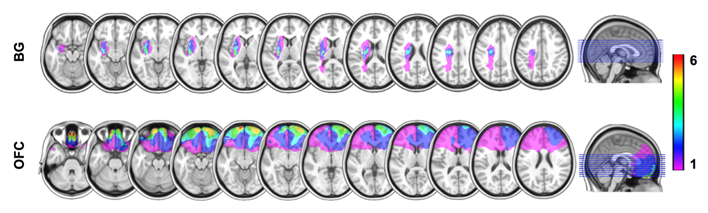

脑损伤区域与计算模型结果

为什么基底神经节受伤,会损害看似简单的非社会情境下的学习决策能力,但不影响看似更为复杂的社会互动中的行为?研究者猜想,策略性学习也许可以通过并行的“计算程序”实现,一种“程序”依赖于基底神经节对奖惩信号的追踪,而另一种则依赖于前额叶皮层对社会信息的处理。基底神经节损伤后,我们的大脑为了弥补前一种计算能力的缺失,调用了源于前额叶皮层、更加高阶和社会性的“程序”来完成策略性行为。然而,一旦社会情境消失,无法借助相关的社会信息推断他人决策时,大脑便不再能启动社会性的“程序”,从而导致了基底神经节受伤的病人在人机互动中的异常行为。通过计算建模,研究者比较了不同条件下不同人群的决策行为背后的学习算法,从计算层面为这一猜想提供了科学支持。

计算模型示意图